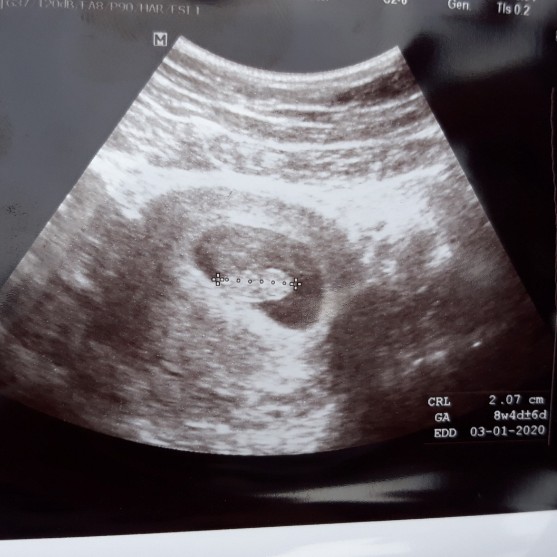

ซาวตอนอายุครรภ์8วีค4วันค่ะ